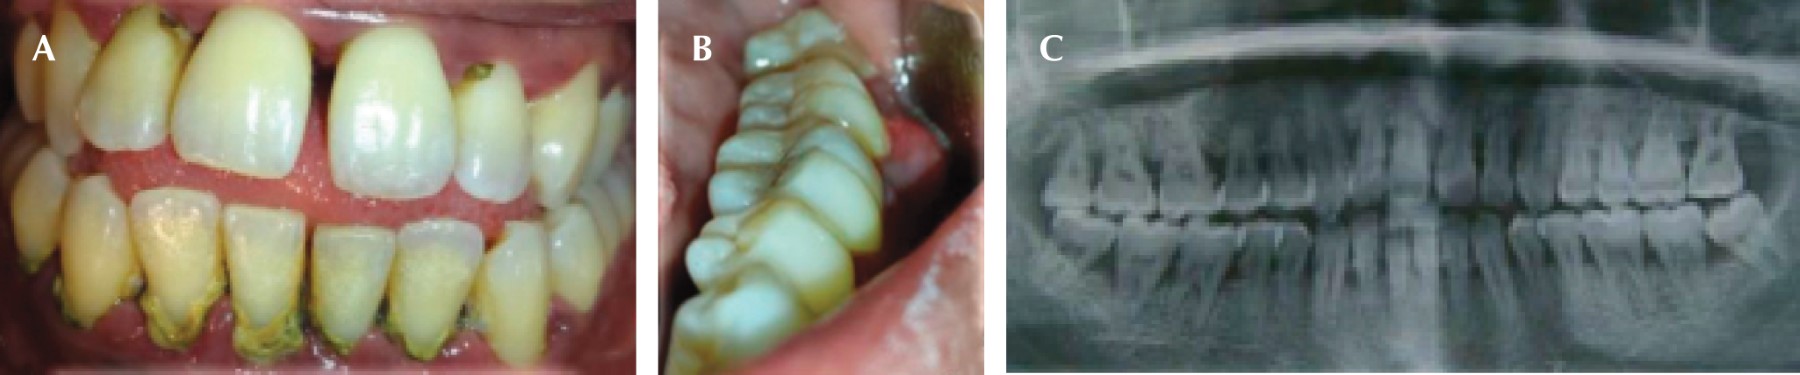

A la inspección clínica se observaron múltiples abscesos periodontales, presencia de placa microbiana (biofilm), cálculo supragingival y subgingival (Figura 5). Con base en estas características y después de haber identificado diversos factores de riesgo, se tomó glucemia por medio de una prueba capilar con valor de 172 mg/dL en ayuno. Con los elementos obtenidos se realizó el diagnóstico periodontal: periodontitis etapa III generalizada grado B (Figura 6).

Se inició la fase I y con base en la adherencia al tratamiento periodontal y un adecuado seguimiento, a pesar de la renuencia de iniciar un tratamiento sistémico se obtuvo una respuesta favorable. El paciente abandona el tratamiento por dos años, a su regreso afirmó que ya es diabético e hipertenso, sometido a tratamiento a través de metformina y enalapril respectivamente. Por medio de radiografías panorámicas y la inspección clínica se observó mayor pérdida ósea generalizada, lo cual mostró la progresión de la enfermedad periodontal, debido al desapego al tratamiento y la suma del factor sistémico (Figura 7A y B). Se inició (nuevamente) la fase I periodontal, realizando múltiples extracciones, debido a las condiciones en las que se presentó. Posteriormente se rehabilitó por medio de una prótesis parcial removible provisional inmediata (Figura 8A y B).